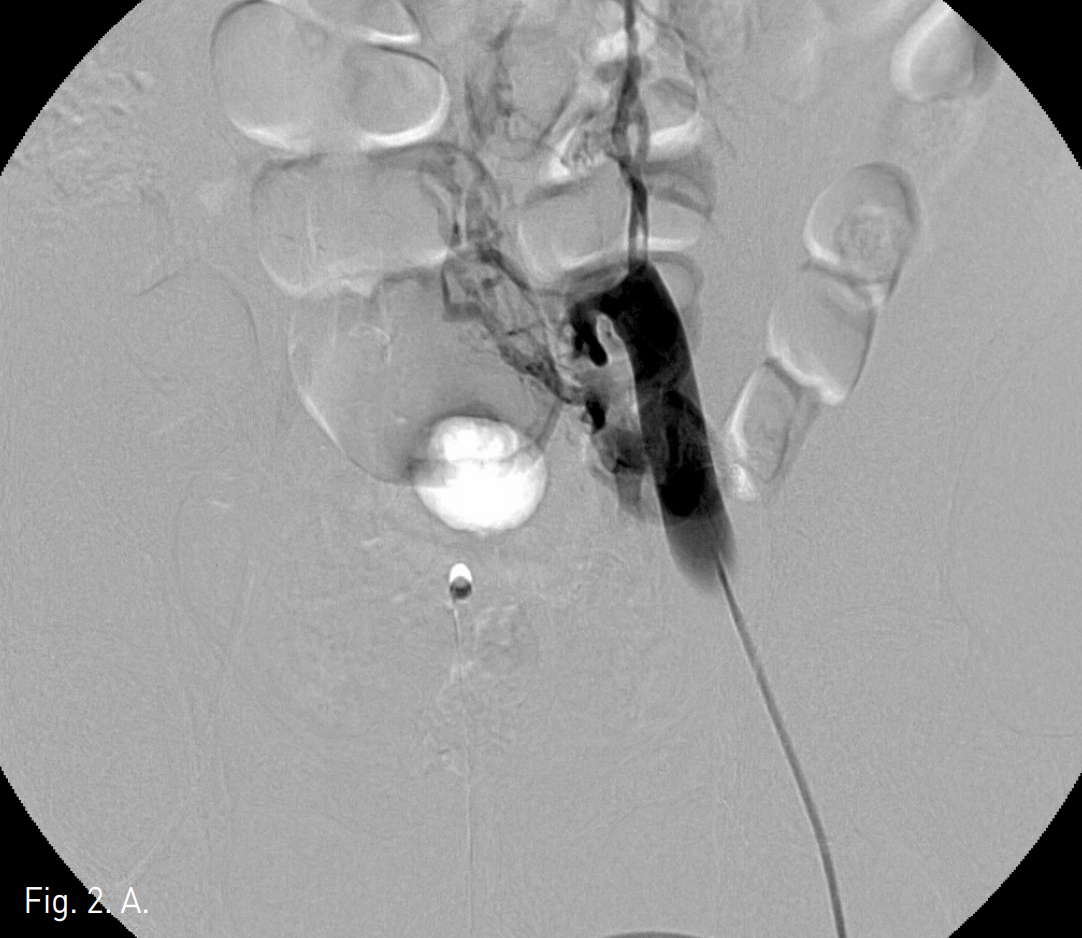

Fig. 2

Venograms obtained after contrast injection in the right (A) and left (B) iliac vein show thrombotic occlusion of both common iliac veins with collaterals.